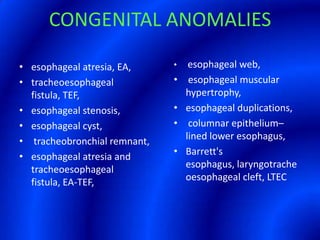

This document provides information about a barium swallow procedure. It begins with an introduction and overview of the embryology and anatomy of the pharynx and esophagus. It then describes the procedure itself, including preparation, technique, views obtained, and indications. Specific conditions that may be examined include pharyngeal and esophageal webs, foreign body impaction, scleroderma, dysphagia, mediastinal masses, and carcinoma. Diagrams are provided to illustrate normal anatomy and various pathological findings.